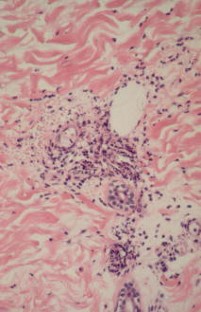

Leukocytoclastic vasculitis

Leukocytoclastic vasculitis (LcV) is the most common form of cutaneous vasculitis. Often LcV results from deposition of immune complexes in the vascular wall. When IgA is the dominant immunoglobulin in these complexes, systemic involvement is likely (Henoch-Schönlein purpura), being more severe in adults. LcV in which immune complexes are composed of IgG or IgM are more often limited to the skin and may additionally show minor systemic involvement. In other forms of LcV additional pathophysiological factors play a role. LcV can also be a presenting or accompanying symptom of severe systemic ANCA-associated vasculitis. In some cases, LcV is a sign of bacteriemia. The aim of diagnostic procedures is to determine the specific type of vasculitis and degree of systemic involvement as well as possible causes. If no trigger or cause can be found, uncomplicated cases of LcV should be treated symptomatically. Corticosteroids are indicated at initial signs of necrosis or ulceration. Chronic recurrent LcV may respond to dapsone or colchicine. Severe systemic vasculitis requires immunosuppressive therapy.

Abb. 1